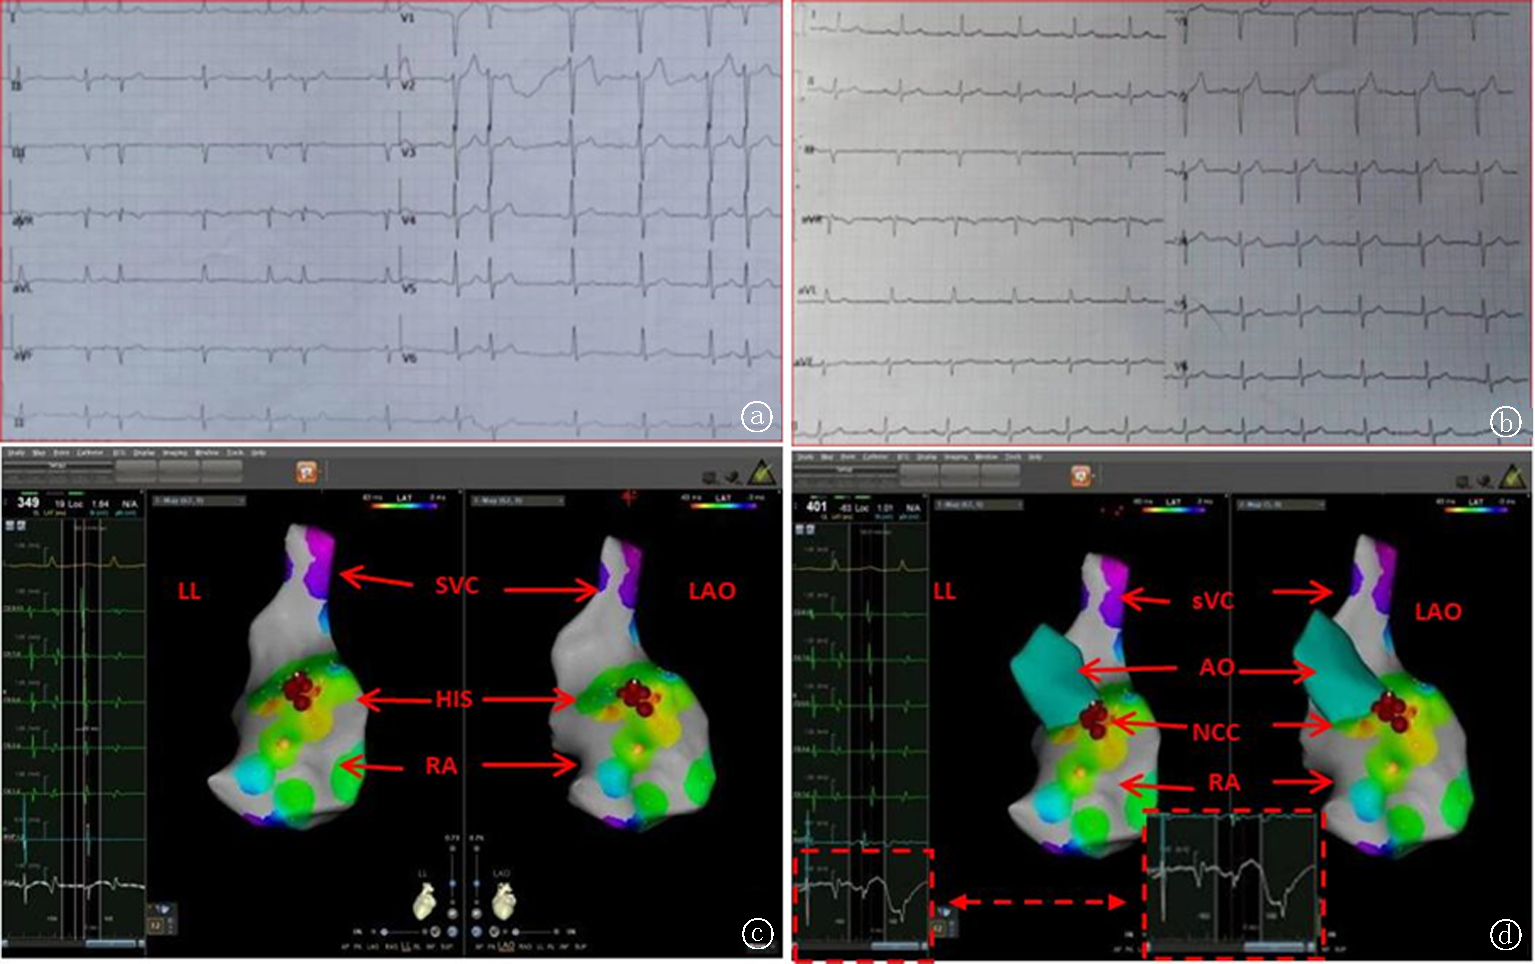

Fig.3 Successful ablation of atrial tachycardias originating near the His bundle region in the NCCA, but ineffective in the right atrium near the His bundle and the left atrium through the interatrial septum a. ECG during arrhythmia: P wave upright in V2-V3, AVL, RP > PR; b. EC after ablation; c. Modeling map of the right atrium: RAO on the left, LAO on the right, yellow is the His bundle, A wave leads the P wave by 51 ms on the interspace surface, ablation ineffective; d. Modeling map of the left atrium: RAO on the left, AP on the; puncture the interatrial septum, local potentials (red) were recorded in the anterior wall of the left atrium in the anterior interspace, which led the P wave by 26 ms, ablation ineffective; e. Modeling map of the aortic sinus: puncture the femoral artery, the aortic sinus was during the arrhythmia, indicating that the local excitation was the earliest to lead the surface P wave by 21 ms, ablation was successful; on the left is RA, on the right is LAO, the yellow dot is the His bundle, the red dot is the earliest to lead the surface P wave by 21Mms, discharge, rial tachycardia terminated; f. Modeling map of the aortic sinus, RA, and LA fusion: RAO on the left, LAO on the, yellow dot is the His bundle, red dot is the earliest to lead the surface P wave in NCC. Note: AP: Anterior-posterior position; RA: Right atrium; LA: Left atrium; AO: aorta